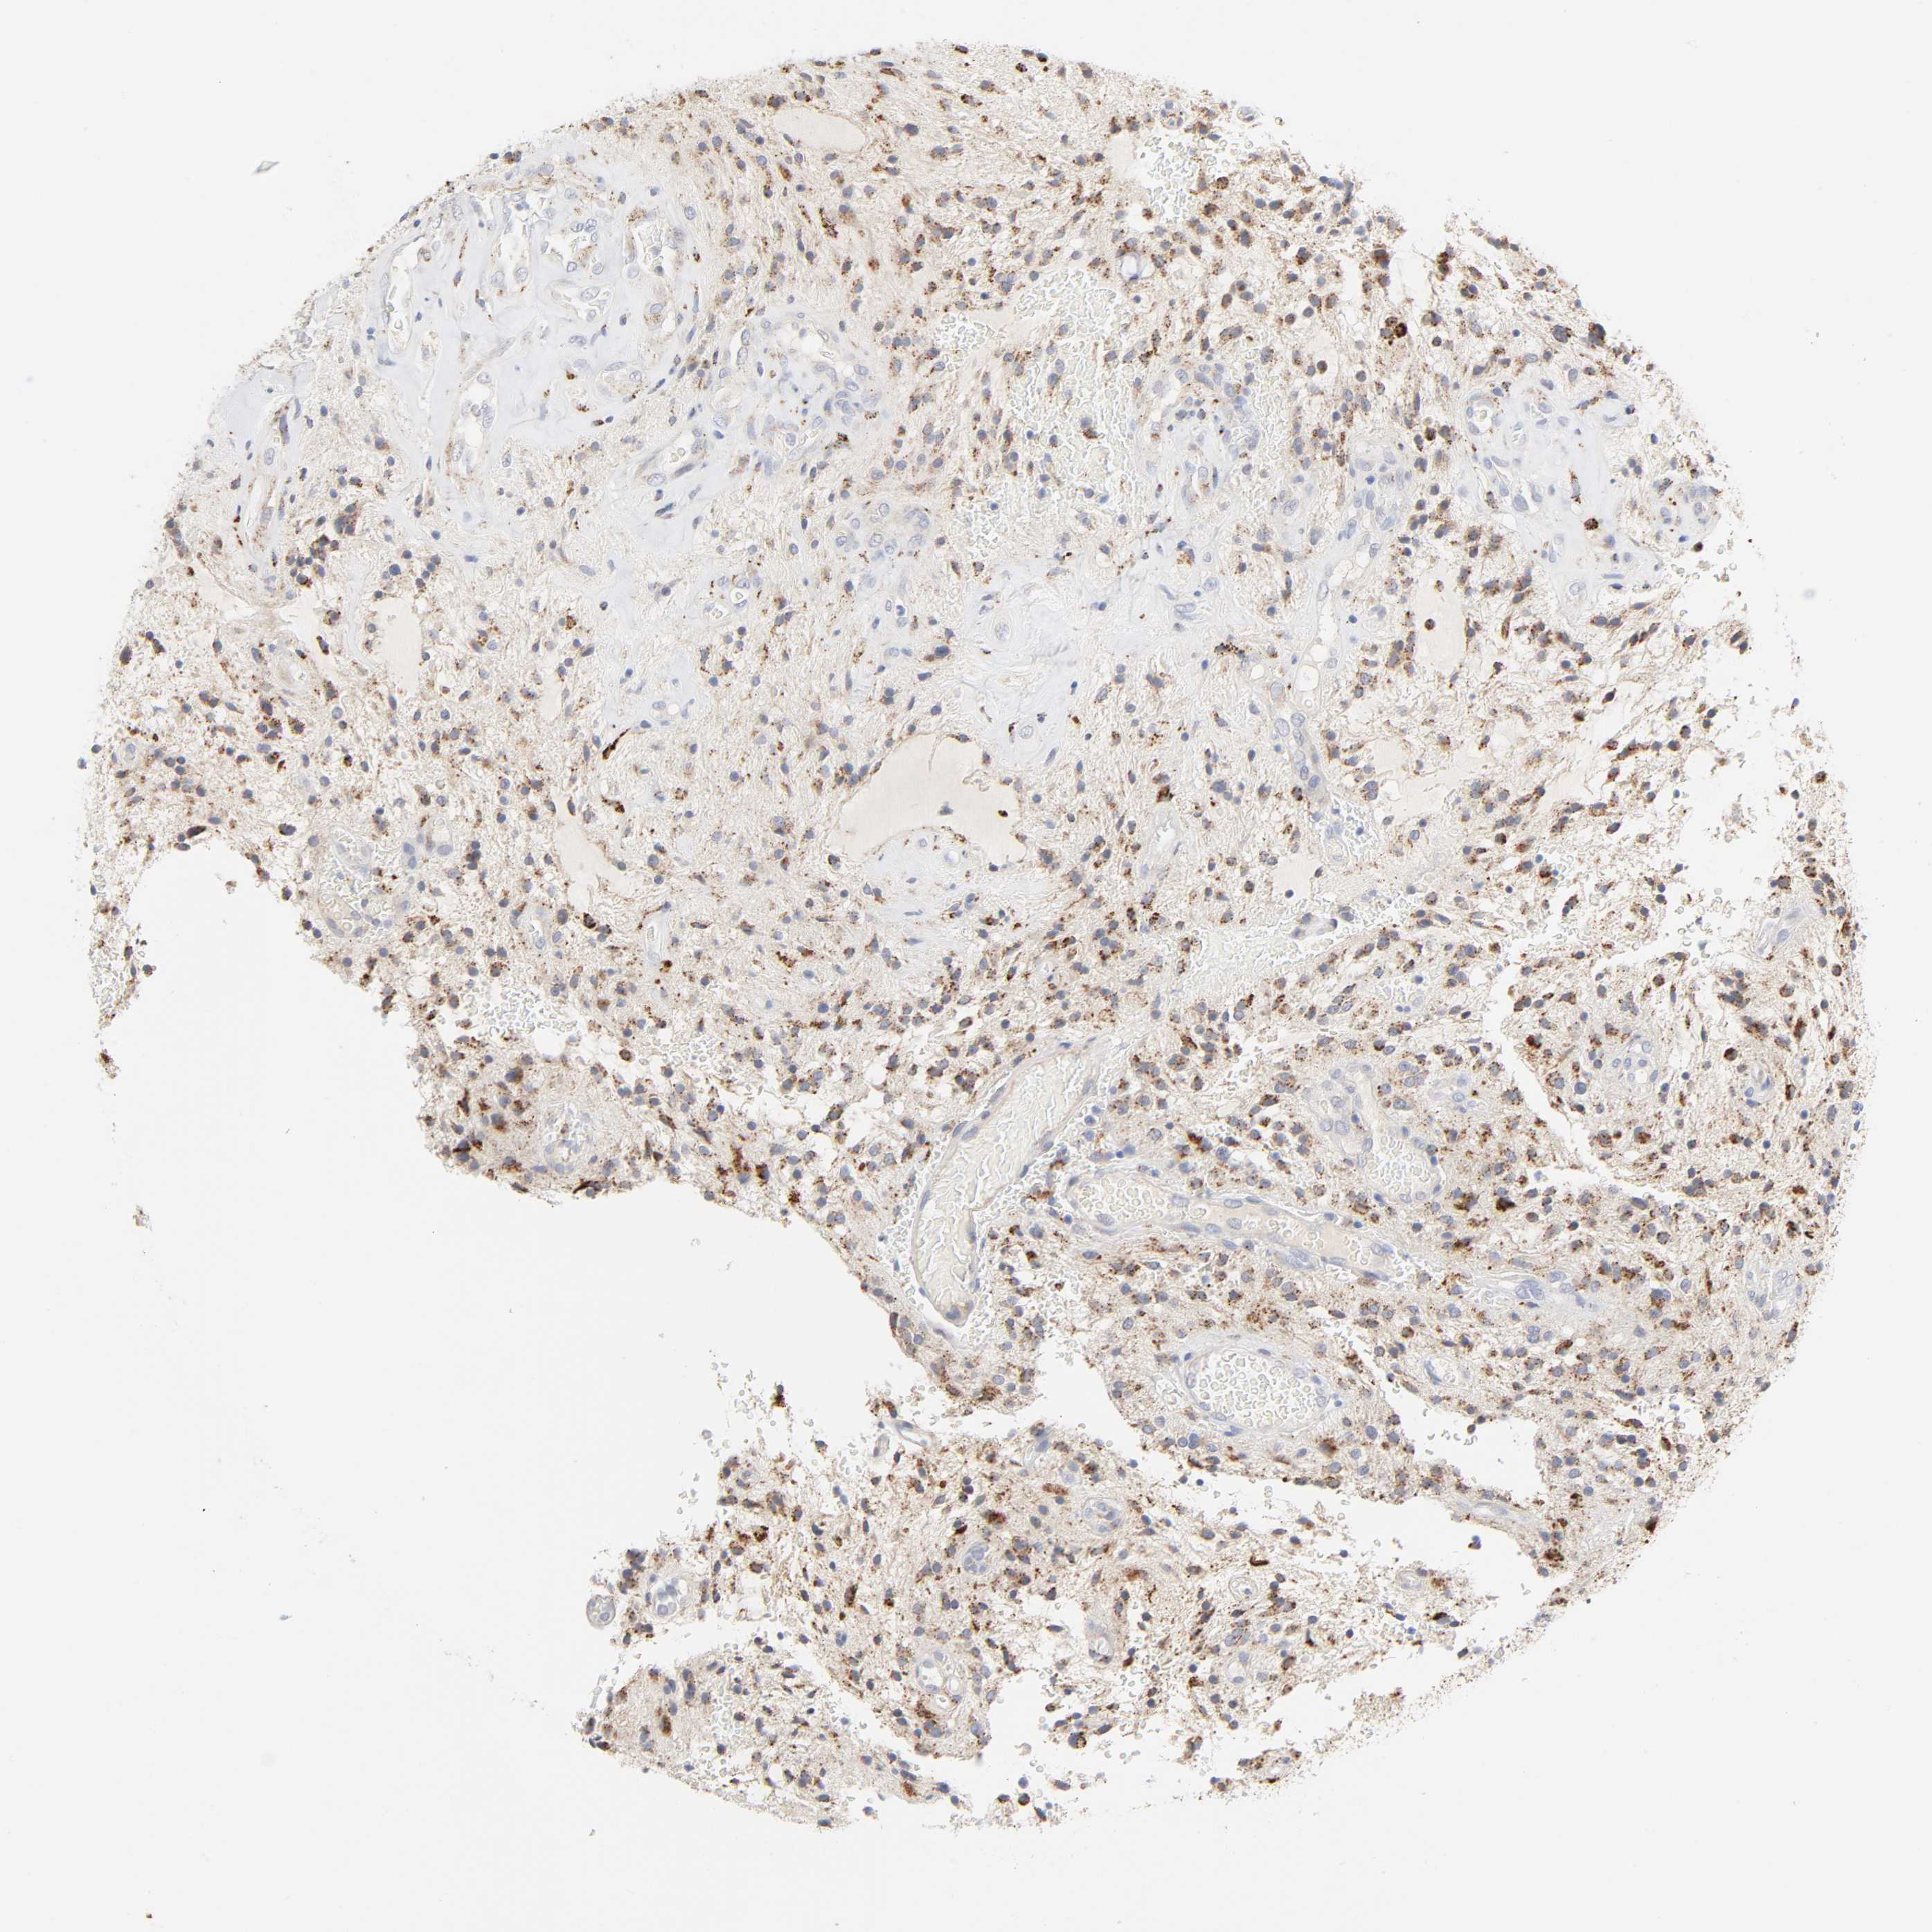

GLIOMA - Protein expressioni

A mouse-over function shows sample information and annotation data. Click on an image to view it in a full screen mode. Samples can be filtered based on level of antibody staining by selecting one or several of the following categories: high, medium, low and not detected. The assay and annotation is described here.

Note that samples used for immunohistochemistry by the Human Protein Atlas do not correspond to samples in the TCGA dataset.

Antibody stainingi

Antibody staining in the annotated cell types in the current human tissue is reported as not detected, low, medium, or high, based on conventional immunohistochemistry profiling in selected tissues. This score is based on the combination of the staining intensity and fraction of stained cells.

Each image is clickable and will lead to virtual microscopy that enables deeper exploration of all samples and also displays staining intensity scores, fraction scores and subcellular localization as well as patient and tissue information for each sample.

Antibody HPA003756

Staining

High

Medium

Low

Not detected

Intensity

Strong

Moderate

Weak

Negative

Quantity

>75%

75%-25%

<25%

None

Location

Nuclear

Cytoplasmic/membranous

Cytoplasmic/membranous,nuclear

Glioma, malignant, High grade

Glioma, malignant, Low grade

Glioma, malignant, NOS